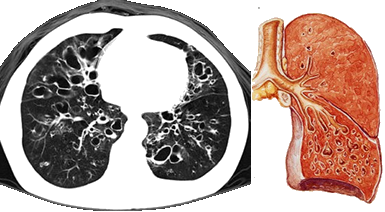

是指各种原因导致的支气管结构破坏,引起支气管异常和持久性扩张。

支气管扩张大多继发于急、慢性呼吸道感染和支气管阻塞。